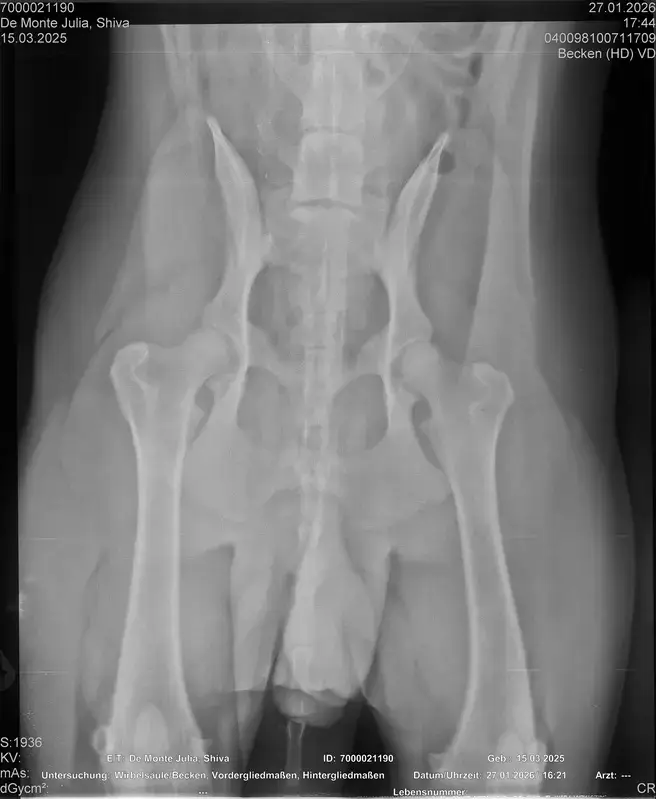

Vorige Woche kam mir Shiva verändert vor, nicht der aufgeweckte Spaßvogel der er sonst ist. Ich dacht vl ist er im Garten iwie blöd ausgerutscht weil unser gesamtes Grundstück über Wochen von einer dicken Eisschicht überzogen war. Er lag viel rum, zuviel da er doch zu den Wirbelwinden unter den Junghunden gehört. Er quetschte sich zum schlafen an mich ran, was auch untypisch für ihn ist. Er ist immer so „iiiii fass mich nicht an“. Ich nehms ihn nicht böse er ist nicht der große Kuschler :D Hat er wohl von mir :D :D aber er pickte nur an mir dran, ruhen ohne Körperkontakt war nicht möglich. Fand ich schön aber da ich wusste dass es nicht Shiva ist machte ich mir schon Sorgen… Am nächsten Tag wollte ich ihn bürsten alles war wie immer, er legte sich hin und sah mir zu wie ich einen Fellberg stapelte. Bei seinen Hinterpfoten hörte ich auf und dachte mir ich fühl mal vorsichtig.. Plötzlich knurrte er mich an vor Schreck weil ich damit überhaupt nicht gerechnet hatte zuckte ich reflexartig zurück (was lt Trainerin ein Fehler war)… Aber ich hab nicht mit einer derartigen Reaktion gerechnet, Shiva hatte schon 2 kleine Verletzungen die ich ohne Probleme verarzten konnte. Am nächsten Tag gings ab zum TA. Mit Maulkorb da ich nichts riskieren wollte. Nach der Untersuchung wo er auch mehrmals knurrte gings ab zum röntgen. Und das riss mir den Boden unter den Füßen weg. Dann die Aussage von der TA „ich weiß sie wollen einen gesunden jungen Hund aber das ist Shiva leider nicht“. Was jetzt? Er ist so ein aufgewecktes Kerlchen, absolute Lieblingsbeschäftigung ist Parcour. Er macht es so gern, ja auch UO und Suchspiele aber das leuchten in seinen Augen wenn wir Geräte machen :( (er macht noch keine schweren Geräte wie A Tafeln oder springen… Aber die seichten macht er mit absoluter Leidenschaft.. Ruhe halten über mehrere Monate… nur langsames gehen oder schnüffeln.. puh ich weiß nicht wie ich ihm verbieten soll zu rennen und zu toben… Vl habt ihr Tipps für mich. Im Anhang der Befund und ein paar Bilder vom kleinen Wirbelwind. <3

• Naja die Diagnose kommt von einem „Facharzt“, lt TA war ihrerseits alles i.O. Sie wollte noch sicher gehen und die Bilder zur weiteren Befundung einschicken und das kam dabei raus. Und der Therapievorschlag beläuft sich auf Ruhe, Ruhe und noch mehr Ruhe. Und einer Schmertherapie von Gabapentin 800mg 1/2 Tablette 2x tgl, Carprodyl 120mg 1 1/2 Tabletten 1x tgl und TamaCan CBD Tropfen 10-15 Tropfen 2x tgl. 1x in der Woche soll ich telefonisch Auskunft geben wie es Shiva geht. Das ganze mal für 14 Tage. Sie meinte noch sie hat viele Junghunde die ein Leben lang Schmerzmittel nehmem müssten. Die Röhrenknochenentzündung heilt in der Regel von selber der Rest gehört beobachtet… Ich weiß im Moment auch nocht so recht.. Er tut mir nur wahnsinnig leid mit sovielen Diagnosen und für mich war erstmal vorrangig ihn schmerzfrei zu bekommen. Das ist er inzwischen und versteht die Welt nicht mehr warum er nicht wie sonst spielen und arbeiten darf. Im Anhang noch Röntgenbilder falls sich jemand damit auskennt bzw Interesse hat..

• Ok, die Röntgenbilder sind aber auch extrem schlecht.

Panostitis ist idR sehr schmerzhaft, aber nicht unüblich und heilt in der Regel von alleine aus, wichtig dabei ist schonen und Entzündungshemmer zu geben, damit das nicht chronisch wird. Ich denke, dass die Akut bemerkbaren Schmerzen hauptsächlich davon kommen. Also da passt die Empfehlung deiner TÄ für's Erste auf jeden Fall.

Wenn dieser Panostitis-schub rum ist, würde ich dem Rest nochmal nachgehen. Man kann bei Dr. Tellhelm ( SV Gutachter) ein privatgutachten in Auftrag geben, das kostet um die 100€. Da kriegst du halt ne konkrete Einstufung und nicht "verdacht auf" und "könnte hiermit ODER damit in Verbindung stehen", etc.

Ich denke aber, dass du für ein Gutachten von Tellhelm nochmal neu röntgen lassen musst, ich finde, dass das Bild der Hüfte (HD und LÜW wird da beurteilt) und die Draufsicht auf die Ellenbogen (nötig zur Beurteilung von ED) unterirdisch sind!